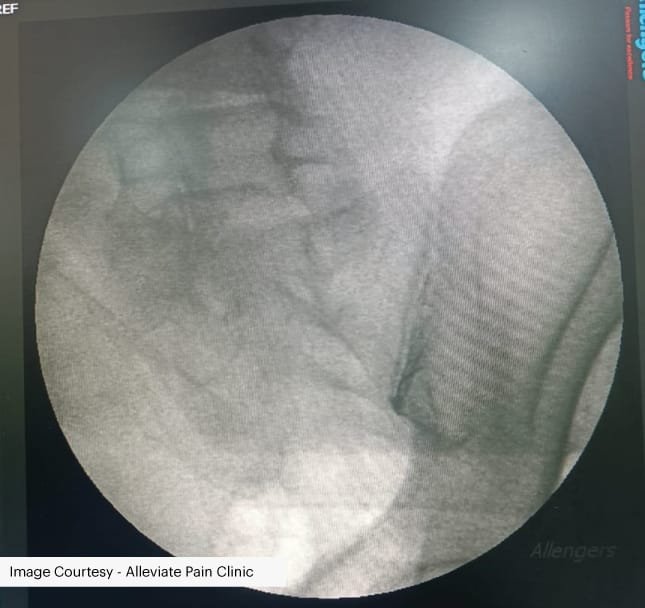

Post scan